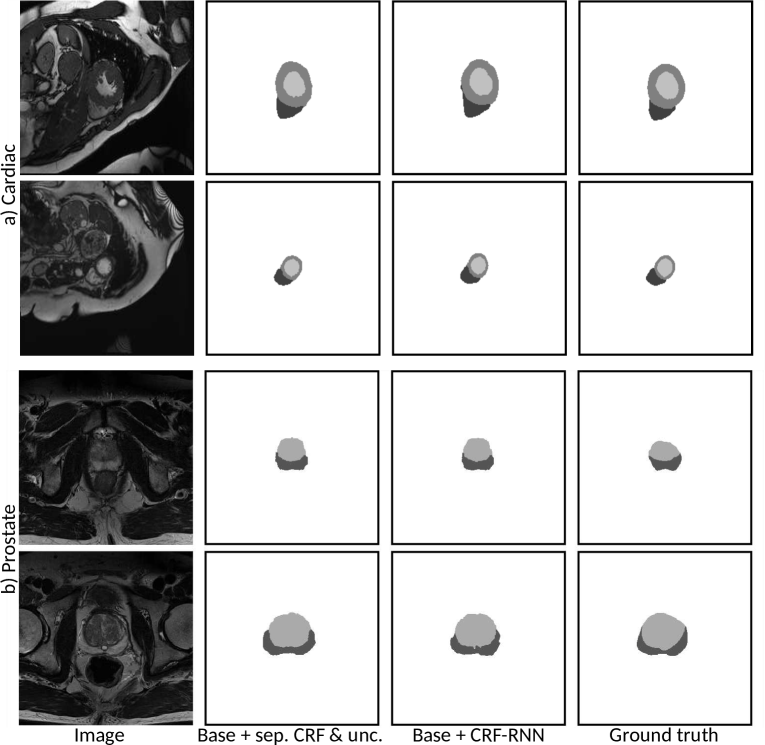

The Dice scores with respect to the reference annotations for all the examined methods and structures are shown in Table 1. Note that ACDC challenge server did not allow for higher precision Dice reporting in the post-challenge phase. Example segmentations for the two best performing methods are shown in Fig. 3 for the cardiac and prostate data, respectively.

Refer to caption

Figure 3: Randomly sampled example segmentations for the two best performing training strategies for the a) cardiac and b) prostate data.

We observe that a) the recursive training regime led to substantial improvements over non-recursive training, b) the dropout based uncertainty was responsible for the largest improvements, c) additional CRF led to further, albeit smaller improvements, d) using CRF-RNN without uncertainty led to similar results as the separate CRF with uncertainty, e) applying dropout uncertainty in conjunction with the CRF-RNN did not lead to additional improvements and performed slightly worse on the prostate. We believe this is due to the CRF-RNN module leading to unusual logit distributions at its input. On average, the training frameworks with 1) CRF-RNN, and with 2) separate CRF and uncertainty performed the best and similar to each other. Future work on integrating uncertainty with the CRF-RNN may lead to further improvements.

Most importantly, the results show that our proposed training strategy allows to learn a pixel-level segmentation network using scribble supervision alone with a remarkably small degradation compared to the fully supervised upper bound. For instance, the performance of the CRF-RNN method is only 4.5% worse on the prostate, and 2.9% worse on the cardiac data compared to fully supervised training. These results are also confirmed by the qualitative analysis. We believe this is likely an acceptable error margin for certain quantification studies where precise border delineation is of secondary importance such as automatic estimation cardiac ejection fractions [2].